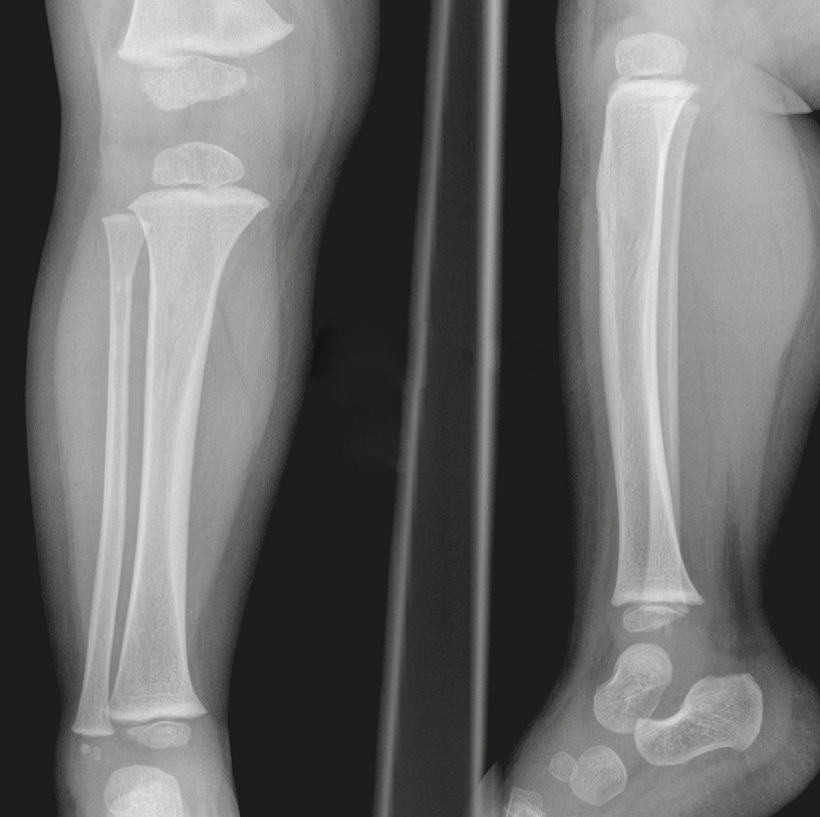

Toddler’s fracture

• When a child first begins to walk

• A nondisplaced oblique or spiral fracture of the midshaft

of the tibia

• Most children present with failure to continue to walk or refusal to bear weight on that extremity

Common sites for Toddler’s fracture

• tibial midshaft

• proximal anterior tibia

• calcaneus

• cuboid